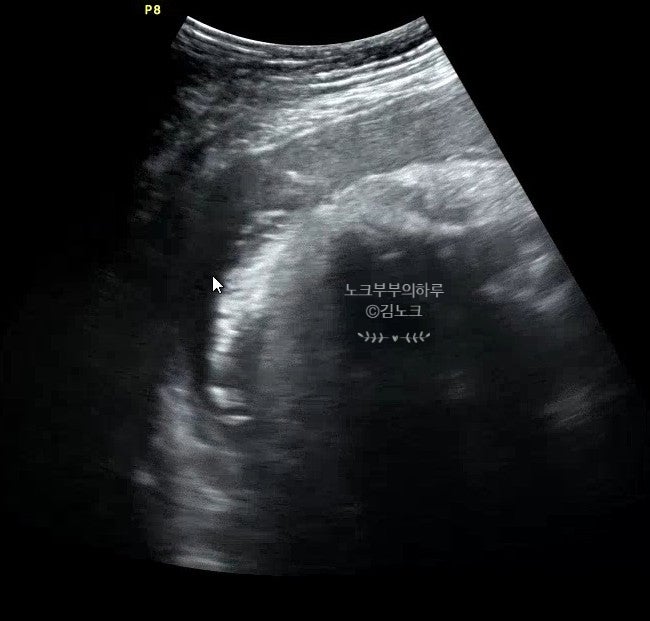

수지미래산부인과 유도분만 김해숙원장님 / 첫째 둘째 출산 비교

#수지미래산부인과 김노크입니다 :) 드디어 둘째 출산 후 조리원에서 써보는 포스팅..! 많이 기다리셨죠,,?...